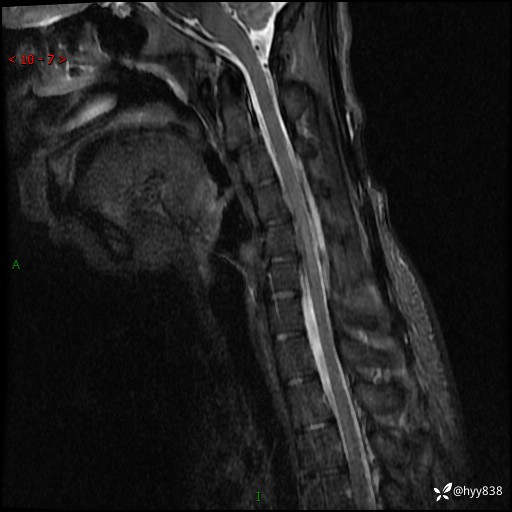

【患者信息】:男,17岁

【主诉】:右手抖动,乏力2年

【检查】:颈椎MRI

【临床诊断】:肌无力